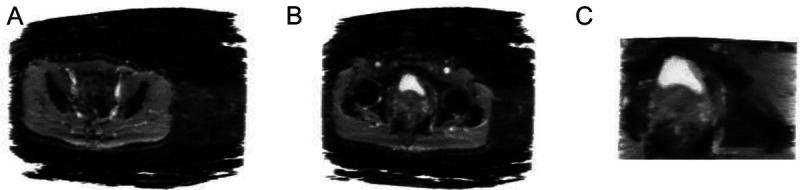

Materials and methods: We examined image sequences of 254 patients with PCa obtained from diffusion-weighted and T2-weighted imaging, using novel MRI sequences before prostatectomy, to elucidate the characteristics of the 3-dimensional (3D) image sequences. The presence of PCa was determined based on the final diagnosis derived from pathological results after prostatectomy. A 3D deep convolutional neural network (3DCNN) was used as the AI for image recognition. Data augmentation was conducted to enhance the image dataset. High-grade PCa was defined as Gleason grade group 4 or higher.